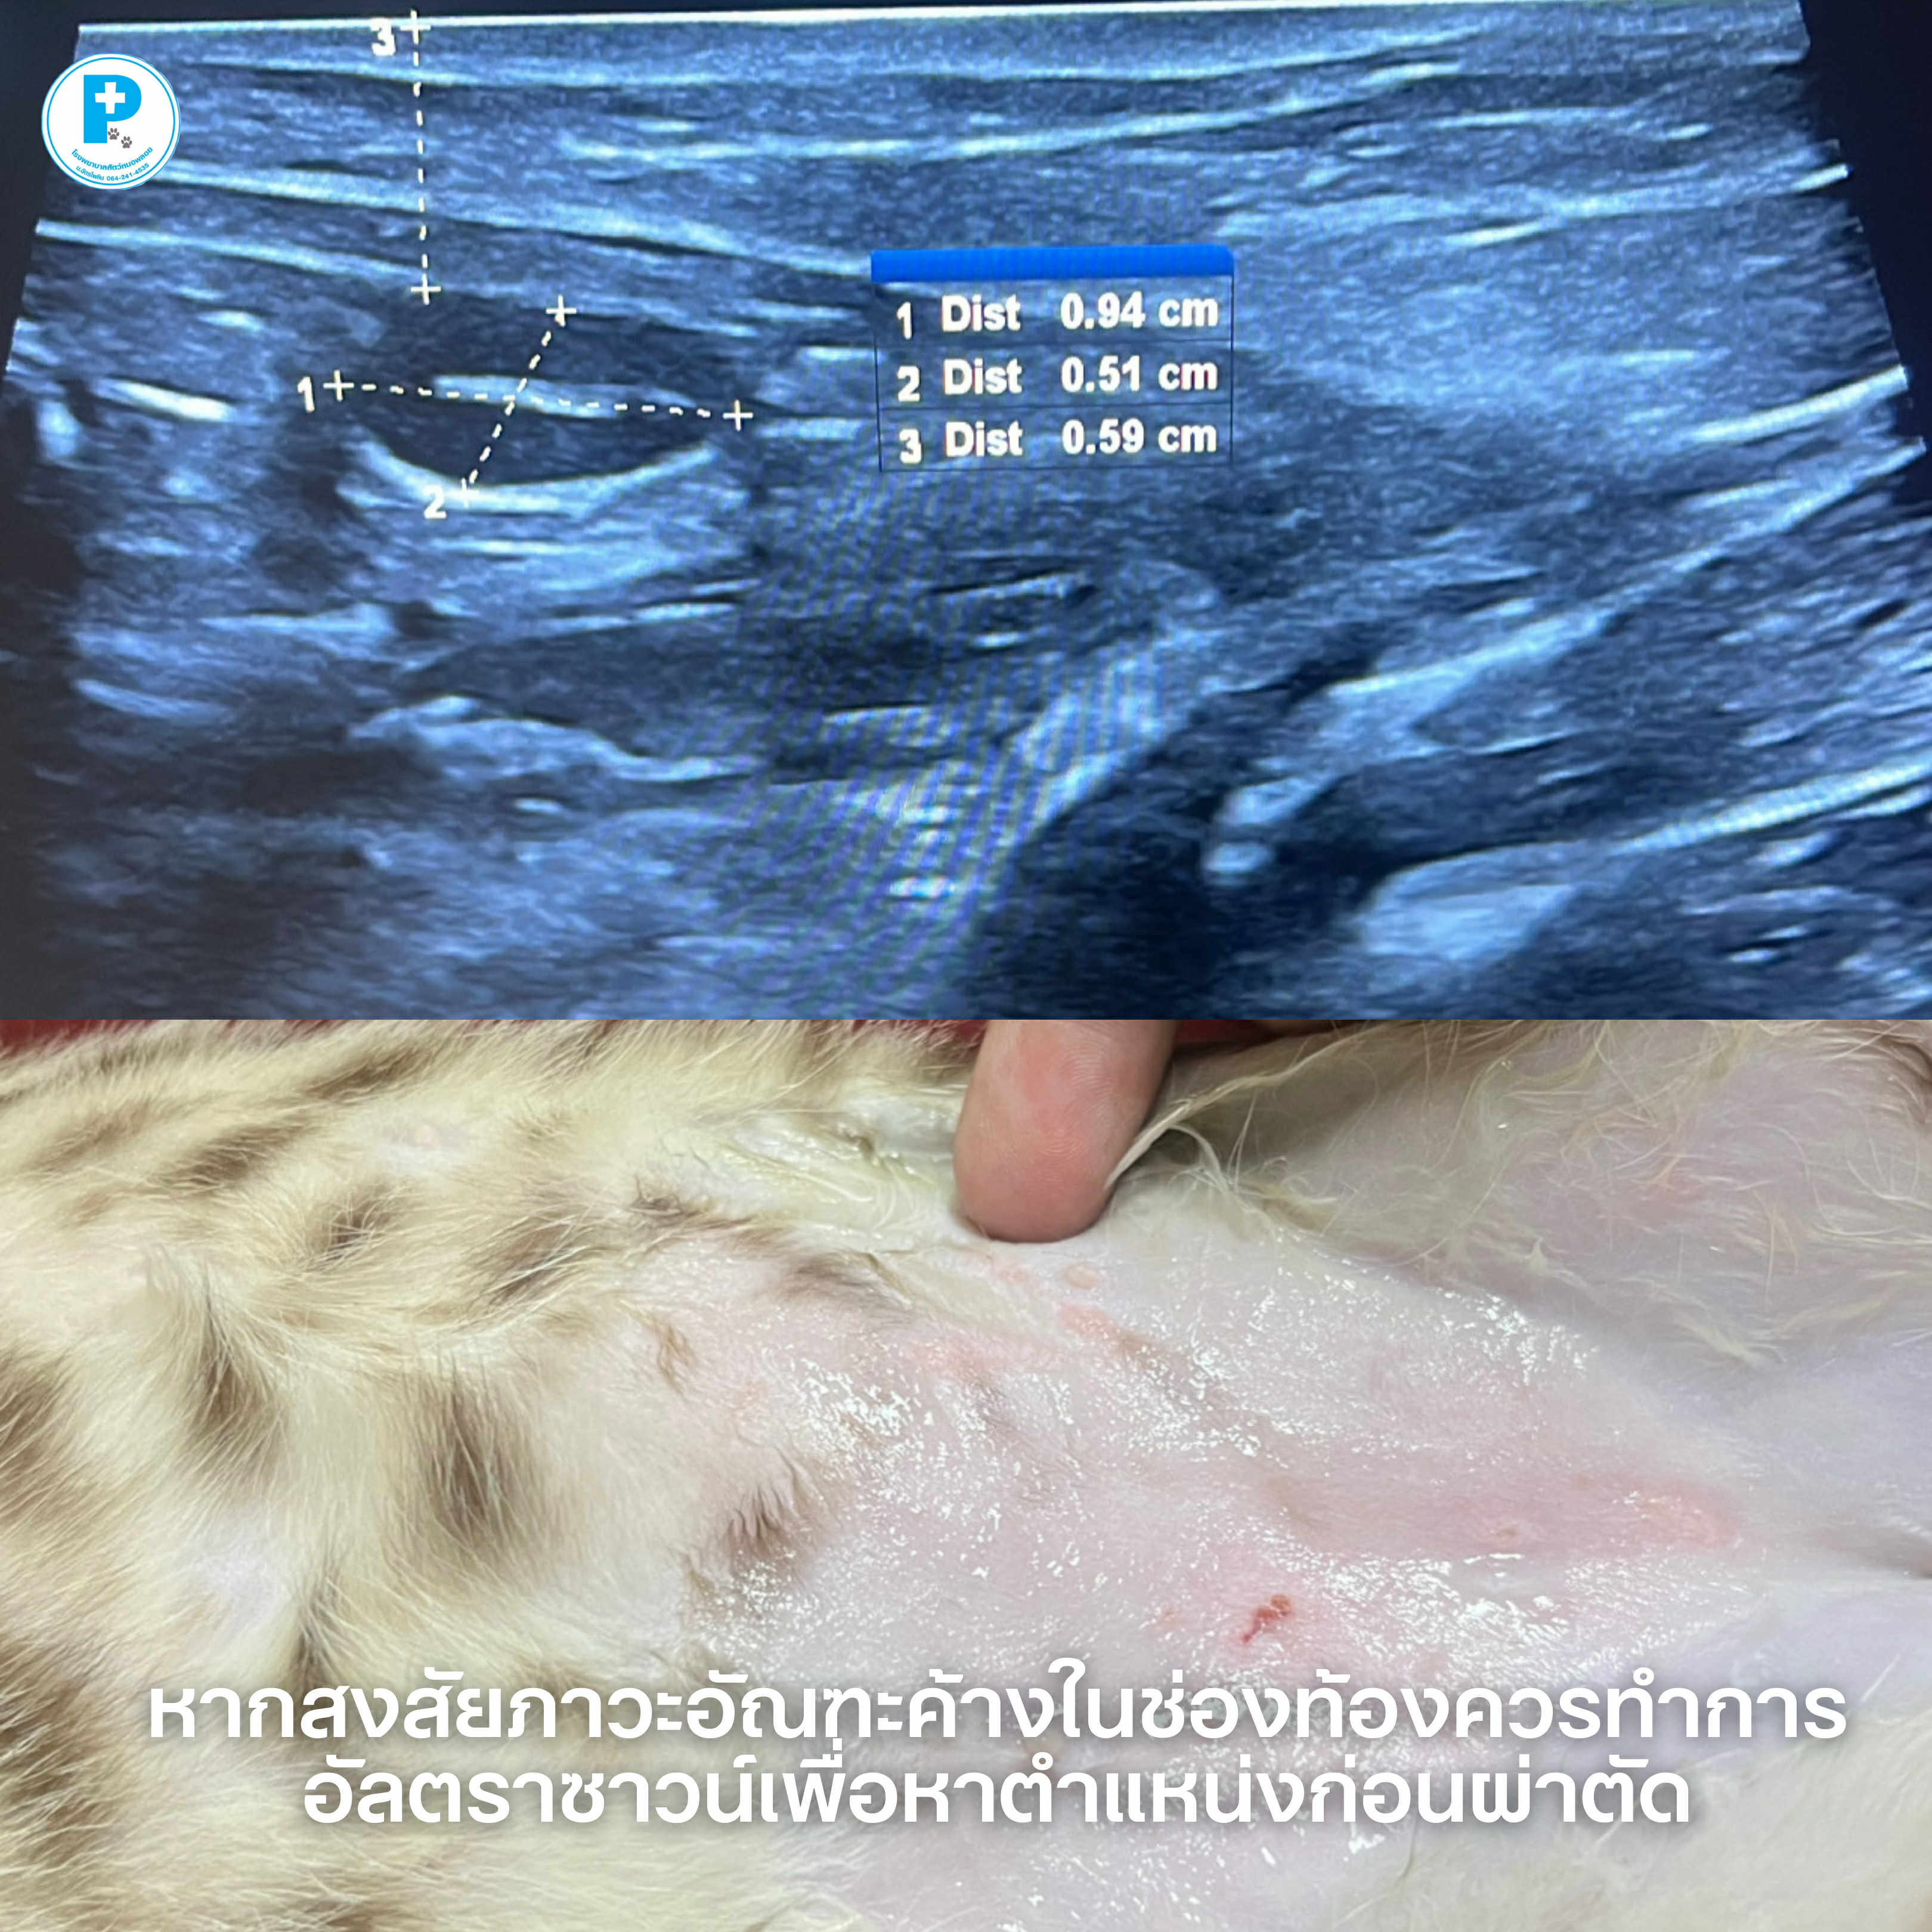

- ภาวะอัณฑะค้างในช่องท้อง (Cryptorchidism)

หลายคนอาจคิดว่า “ทำหมันตัวผู้” คือการผ่าตัดเล็กธรรมดา

แต่ในบางเคส อัณฑะไม่ได้อยู่ในถุงอัณฑะ

อัณฑะอาจค้างอยู่ใน• ช่องท้อง

• ขาหนีบ

• หรืออยู่ในตำแหน่งผิดปกติอื่น

ดังนั้นก่อนผ่าตัด เราจึงแนะนำ อัลตราซาวน์เพื่อหาตำแหน่งอัณฑะ

ช่วยให้

วางแผนผ่าตัดแม่นยำ

ลดเวลาในการผ่าตัด

ลดการบาดเจ็บต่อเนื้อเยื่อ

เพิ่มความปลอดภัยให้คนไข้

เคสนี้ทำ Castration + Abdominal Cryptorchidectomy ผ่าตัดทำหมันร่วมกับผ่าตัดนำอัณฑะที่ค้างในช่องท้องออก

ภาวะอัณฑะค้าง ไม่ควรปล่อยไว้เพราะมีความเสี่ยงต่อ

การเกิดเนื้องอกในอัณฑะ

การบิดขั้วอัณฑะ (testicular torsion)

ปัญหาฮอร์โมนผิดปกติหากสงสัยว่าน้องมีอัณฑะลงไม่ครบ สามารถพาเข้ามาตรวจประเมินได้

ผ่าตัด: สพ.ญ.ณัฐฐ์ธวรรณ โสภิพันธ์ (หมอพลอย)

อัลตราซาวน์/เรียบเรียง: น.สพ.นรภัทร โสภิพันธ์ (หมอพีท)